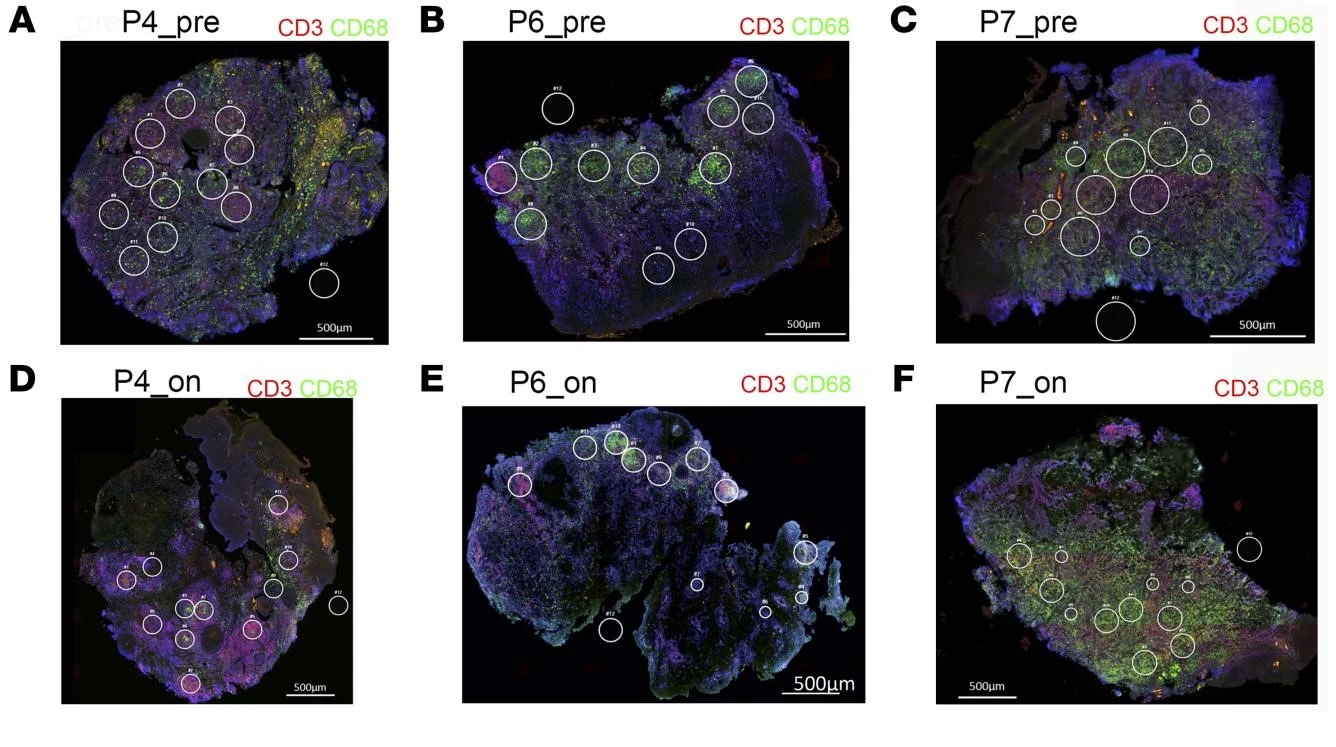

The lesion samples revealed that SSG treatment caused differential expression of immune-related genes, including immune checkpoint molecules. Spatial profiling and RNA fluorescence in situ hybridization (FISH) showed that the expression of PD-L1 and indoleamine 2,3-dioxygenase 1 (IDO1) proteins were reduced within the lesions during treatment. 7 Furthermore, these checkpoint molecules were expressed in higher quantities by parasite-infected immune cells than non-infected controls.

Researchers discovered that early reduction in PD-L1 (but not IDO1) expression was predictive of the rate of clinical cure (hazard ratio = 4.88) and paralleled the reduction in parasite load. It thus appears that the anti-leishmanial activity of antimonial drugs is achieved through the reduction in checkpoint inhibition on T cells. Since this new data indicate that PD-L1 expression is predictive of clinical response rate to SSG treatment in Sri Lankan patients with CL, it is possible that PD-L1 could represent a novel treatment approach for leishmaniasis.

The StrataQuest contextual image analysis software was fundamental to the feasibility of this investigation. It enabled single-cell analysis, the analysis of co-expression of IDO1 and PDL1, and detection of the intracellular leishmaniasis parasite. 9

Quantification of IDO1, PD-L1, CD3 Amastin, and CD68 was performed using StrataQuest Analysis Software, which segmented nuclei based on the signal from the DAPI channel and then built and expanded a mask over staining of IDO-1/ PD-L1.